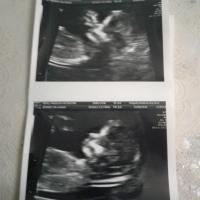

doctors fond a chogenic bowel😔 on my baby girl on the ltrasond.. 'm soo worried and scared for her and know sholdnt bt can't help it ... any story...